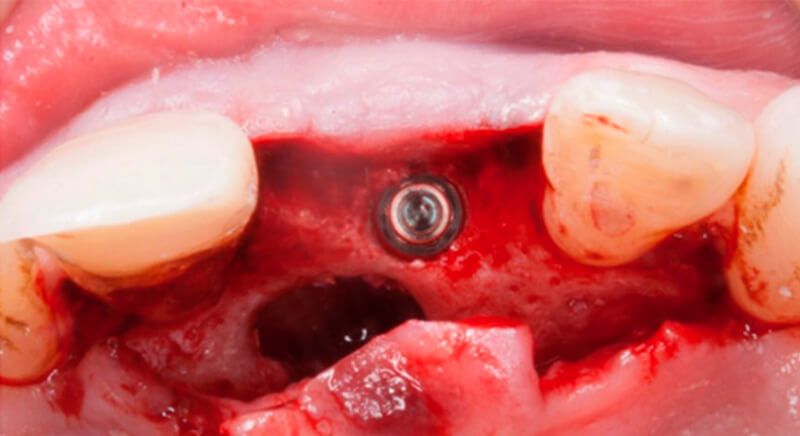

During the digital planning for the implant, with Implant Studio (3Shape) guided surgery software, significant bone defects due to the patient's anatomy were discovered. Placing the implant in the correct position for the prosthesis presented bone dehiscence in the vestibular area, and another bone defect in the palatine area due to the patient's large nasopalatine canal.

This information enabled us to rule out the option of surgery without a flap, as regeneration simultaneous to surgery would be needed, so the idea of using guided surgery was maintained.

The guided surgery was performed by lifting a full thickness mucoperiosteal flap. A Biomimetic Ocean CC implant, diameter 3.5mm and length 10mm, was inserted using the surgical guide in the ideal three-dimensional position and the defects were regenerated with xenograft and reabsorbable membrane, the nasopalatine duct on the palatine side and the area of dehiscence on the vestibular.